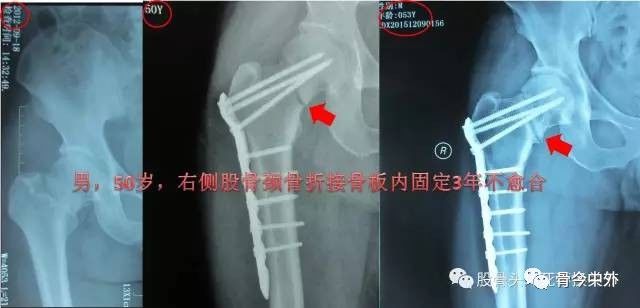

股骨颈骨折应用接骨板固定创伤大、失败率较高,不建议常规应用。

图11?男,50岁,股骨颈骨折接骨板内固定3年不愈合